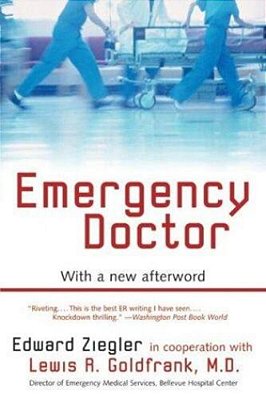

A hundred and thirty years after it was first published, Sarah Orne Jewett's story of a young medical woman remains an incisive rendering of the dilemmas of gender, society, and self. Nan Prince first becomes interested in medicine as a child, as the ward of the widowed physician Dr. Leslie. In time she becomes his protégée. But when she enters medical college, she realizes that she will have to choose between marriage and her career, between the demands of her society and her obligations to her true self. Inspired by Jewett's own interests and by her father, A Country Doctor portrays a world very much in flux and Nan, ultimately, as a woman with a new world opening to her. For more than seventy years, Penguin has been the leading publisher of classic literature in the English-speaking world. With more than 1,700 titles, Penguin Classics represents a global bookshelf of the best works throughout history and across genres and disciplines. Readers trust the series to provide authoritative texts enhanced by introductions and notes by distinguished scholars and contemporary authors, as well as up-to-date translations by award-winning translators.

| ISBN | 9780143039266 |

| Autor(a) | Jewett, Sarah Orne |

| Editora | Penguin Classics |

| Ano de edição | 2005 |

| Páginas | 271 |

| Acabamento | Brochura |